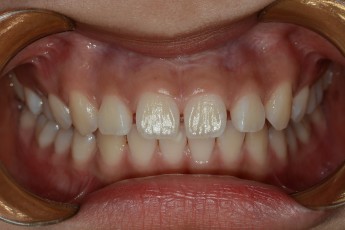

Before

After